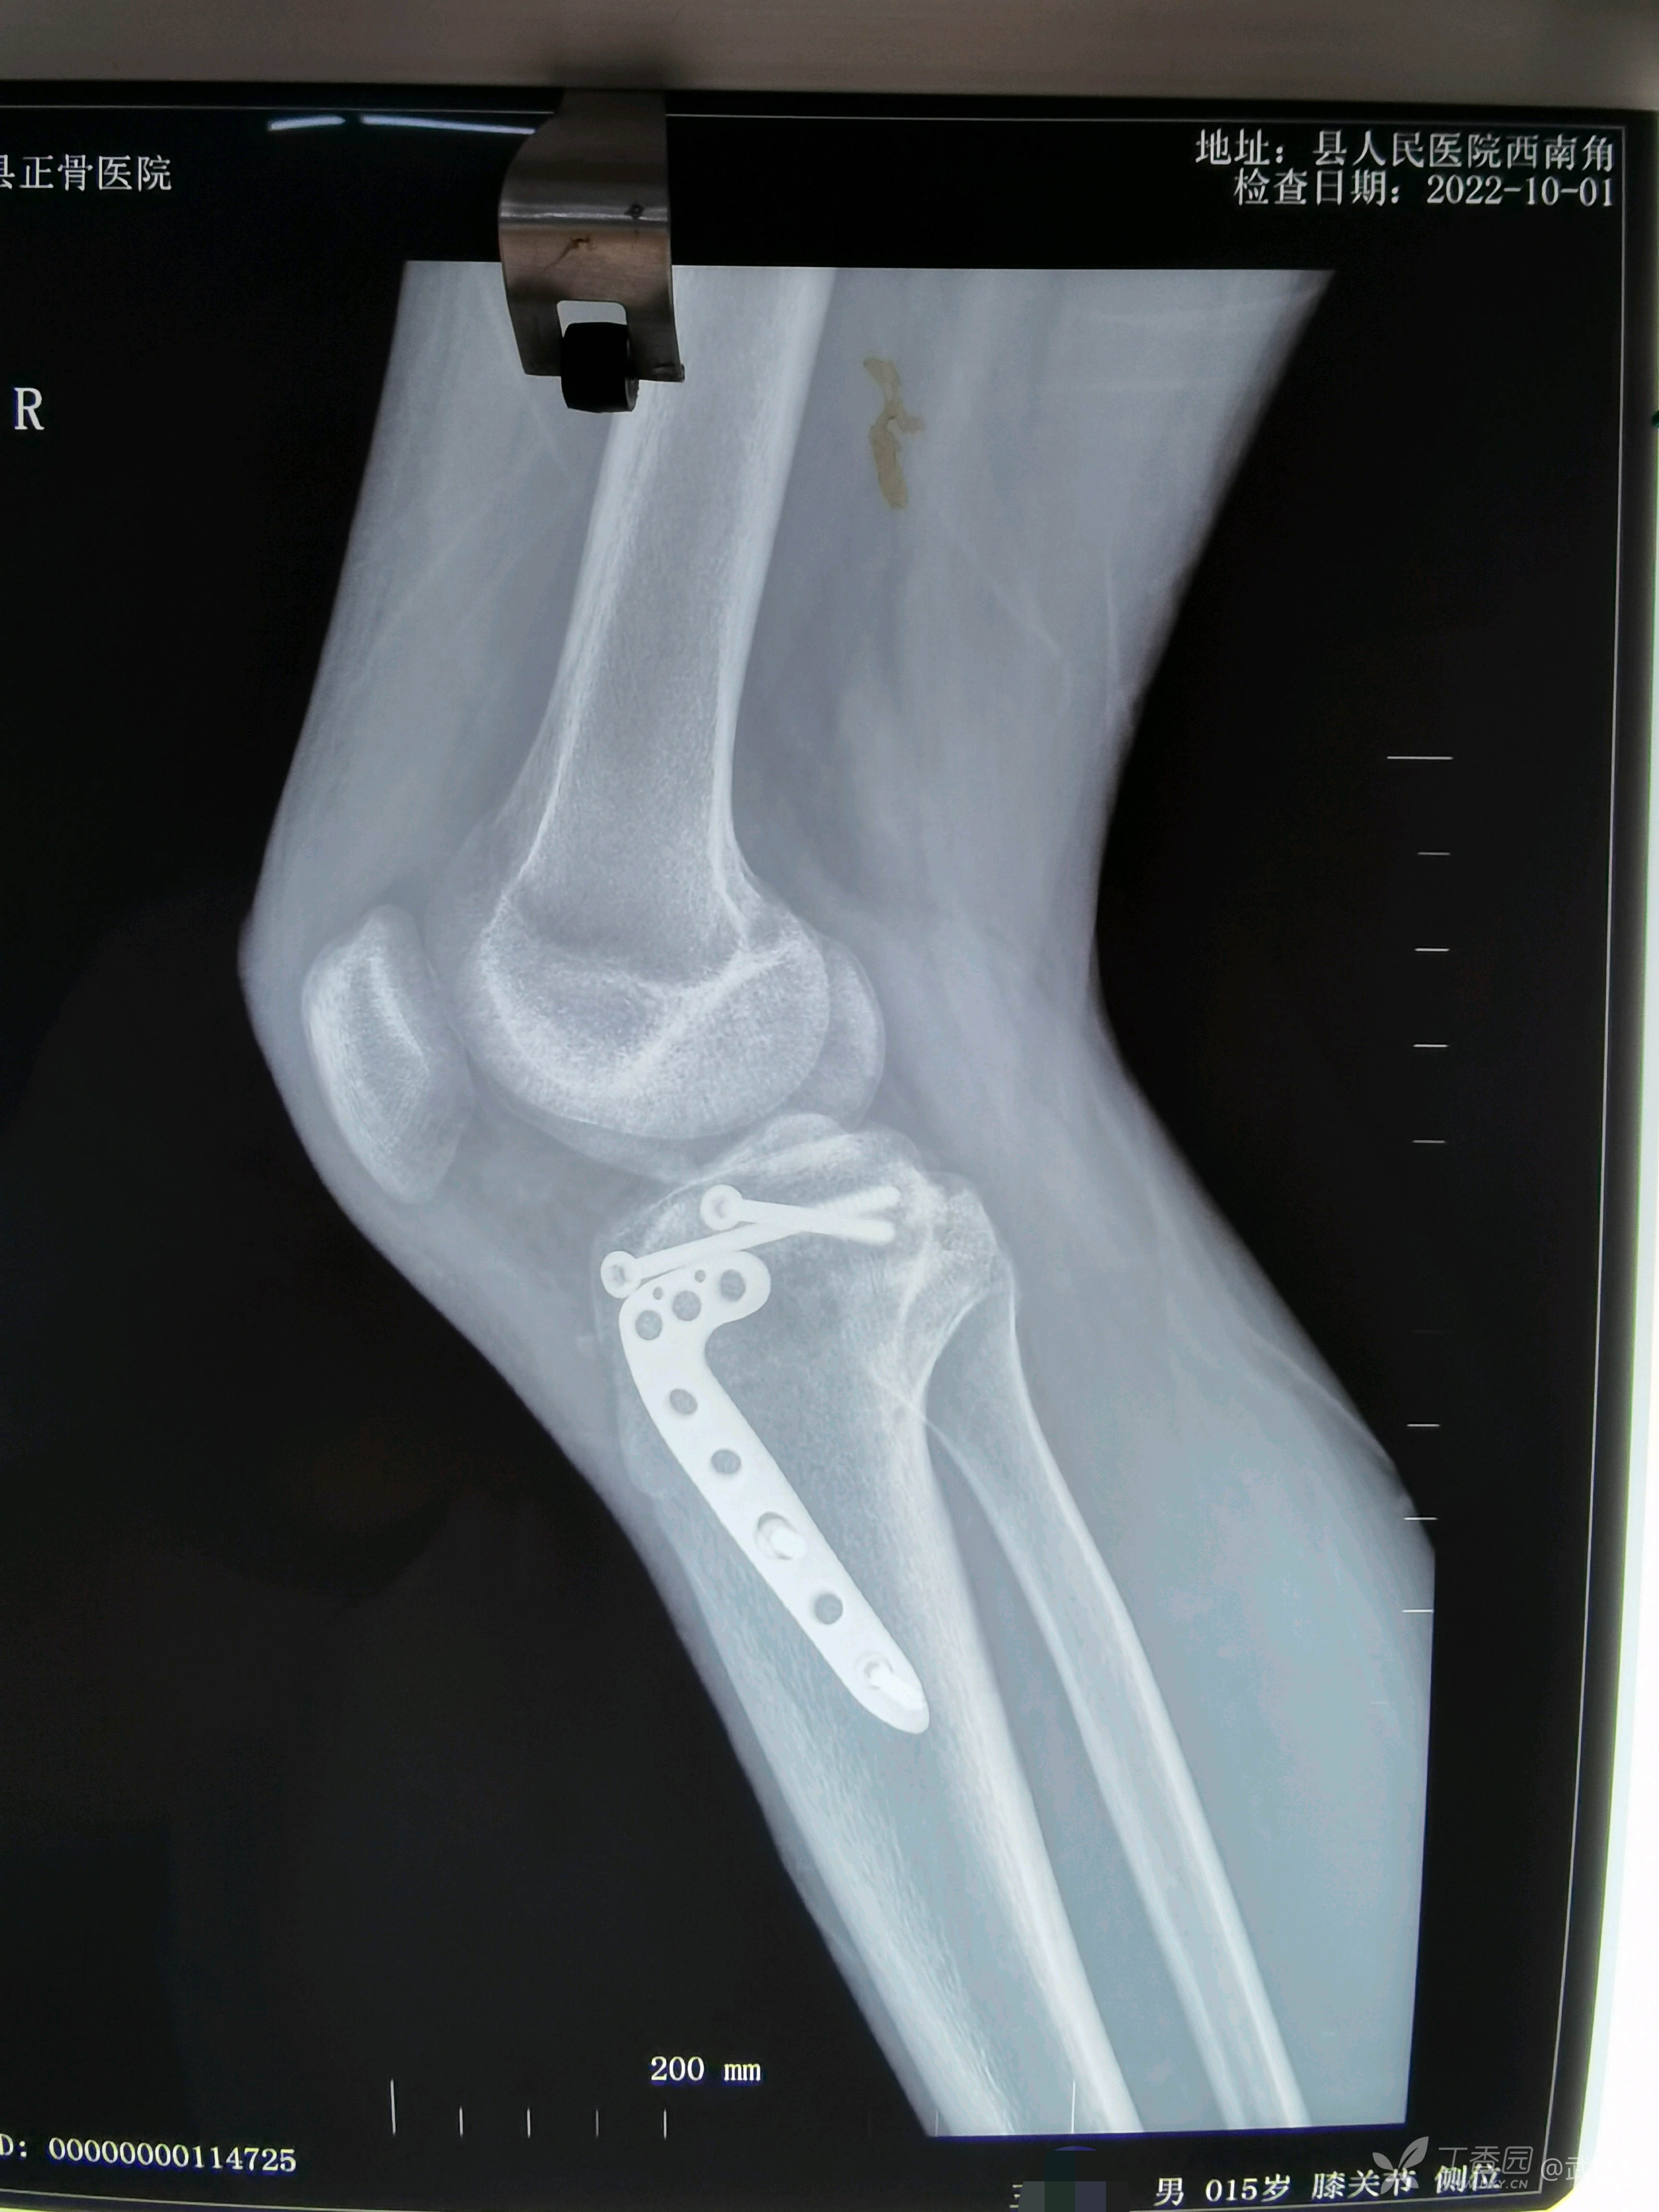

切口一期愈合,出院后疫情爆发,他们家处于风暴眼中心,无法复查,今日术后两月复诊

孩子行走几乎看不出来是才做过手术两个月。